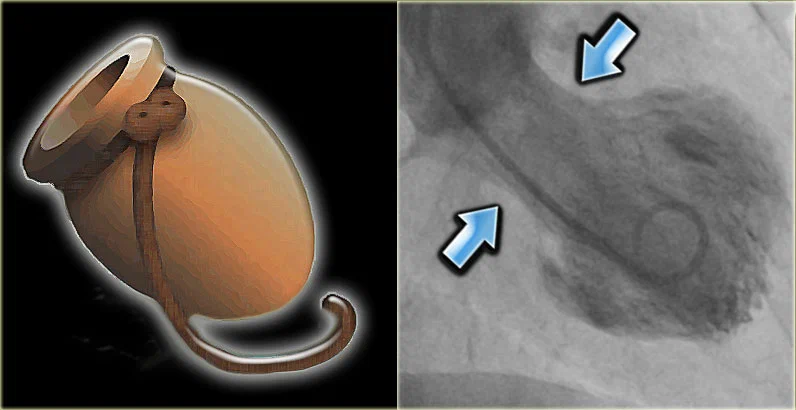

Визуальные тесты, например, коронарная ангиограмма, покажут, что нижняя левая камера сердца становится больше, чем обычно, и что сам орган работает не так, как должен.

Но когда им выполняют ангиограмму (стандартный тест, используемый для определения того, какие артерии блокируются при сердечных приступах), у них не выявляется никаких закупорок или сгустков крови. Тем не менее, у них затронута большая область сердечной мышцы, которая работает неправильно. У пациентов с синдромом разбитого сердца клетки миокарда «оглушены» адреналином и гормонами стресса, но не убиты.